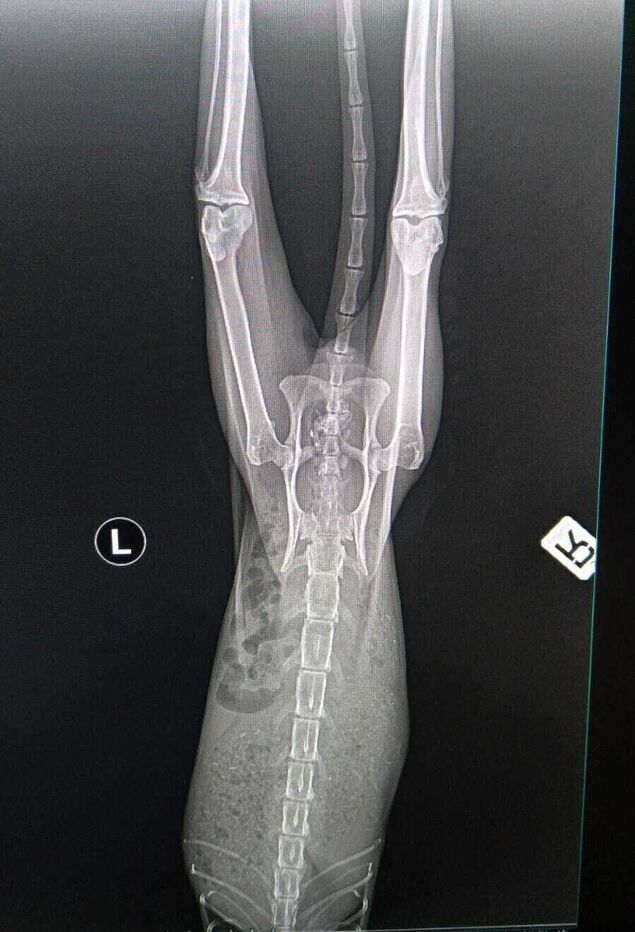

"Wenn wir das auf den Röntgenbildern nicht nachweisen könnten, glaubt uns das niemand", behauptet Birgit Block, Vorsitzende des Cuxhavener Tierheim-Vereins "Eine Pfote, ein Versprechen": "Es ist schier unglaublich, was dieser lieben Katze mitten in Cuxhaven widerfahren ist."

"Was bewegt Menschen, so etwas Grausames zu machen?", fragt Birgit Block empört. Denn eine aufgelesene Katze sei mit einer Schrotflinte angeschossen worden. Danach habe sich das Tier kaum bewegen können und auf seinen Tod gewartet. "In dieser Zeit des Wartens hat sie wahnsinnig abgebaut und sich ihr Sprunggelenk kaputt gelegen", berichtet die Tierschützerin.

Derzeit sei die Katze medikamentös abgedeckt. "Wir gucken, wie der Verlauf in den nächsten 14 Tagen ist. Von einer OP wird erst mal abgesehen, da es zu kompliziert wird", erklärt die Tierheim-Vereinsvorsitzende. Die Tierschützer würden sich freuen, "wenn wir einen Paten für diese zauberhafte Samtpfote finden könnten".